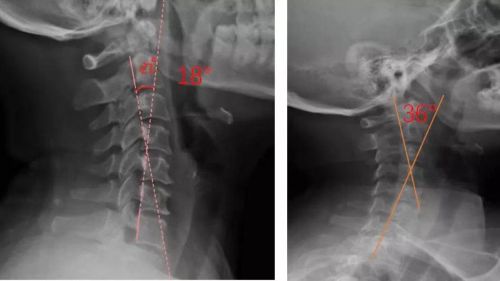

我們通過(guò)對(duì)頸部進(jìn)行光學(xué)掃描與頸椎側(cè)位X光檢查,測(cè)量頸椎曲度,由專業(yè)矯形器師結(jié)合患者的情況設(shè)計(jì)個(gè)性化頸椎枕,部分或全部3D打印工藝制作完成,矯正頸椎的生理曲度?;颊哌m配后拍攝X光片,做到精準(zhǔn)矯正與治療,避免使用不適和矯枉過(guò)正。

患者適配前后側(cè)位X光,佩戴前18°,適配后36°

對(duì)于頸椎病患者,合理設(shè)計(jì)的頸椎枕,能夠緊密適合頸椎,矯正頸椎生理曲度;再根據(jù)頸椎曲度改善情況,隨時(shí)間慢慢調(diào)整3D打印頸椎枕曲度,使變直的頸椎逐漸形成正常的生理曲度,改善頸肩痛的癥狀。